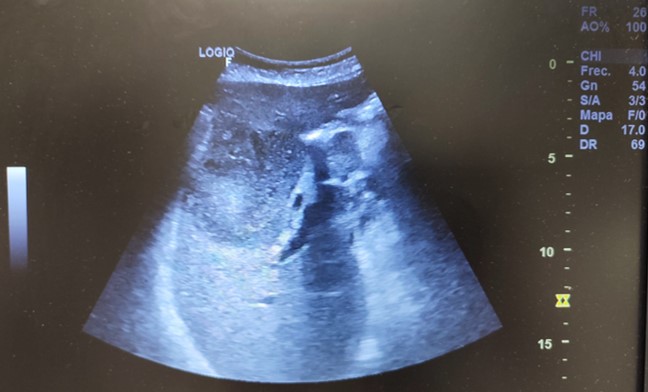

Ecografía abdominal, en la que se identifica masa hepática hipoecoica, heterogénea, de márgenes parcialmente lobulados, de 6.8 cm de diámetro, en región vesicular, con aumento de vascularización y dilatación de via biliar intrahepática. Impresiona de conglomerados adenopáticos en hilio hepático. Páncreas, bazo y riñones normales. No líquido libre intraabdominal.